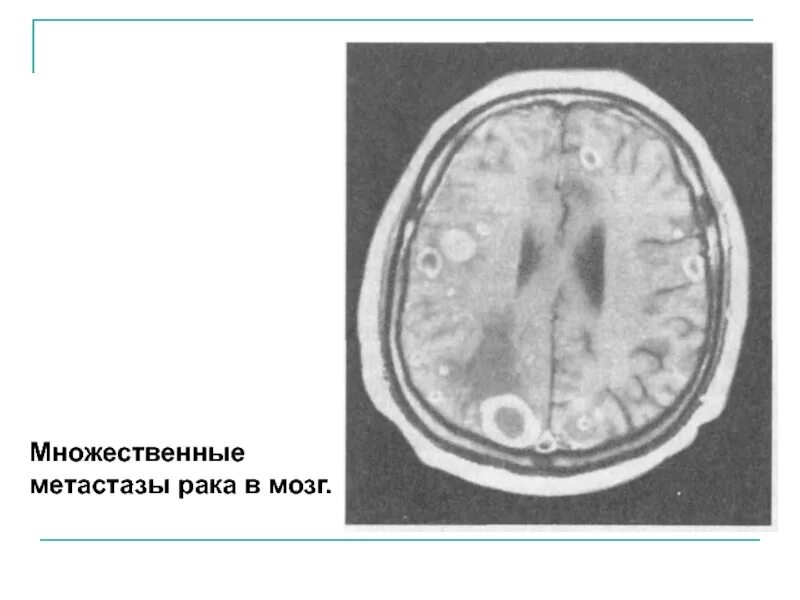

Метастазы головного мозга кт